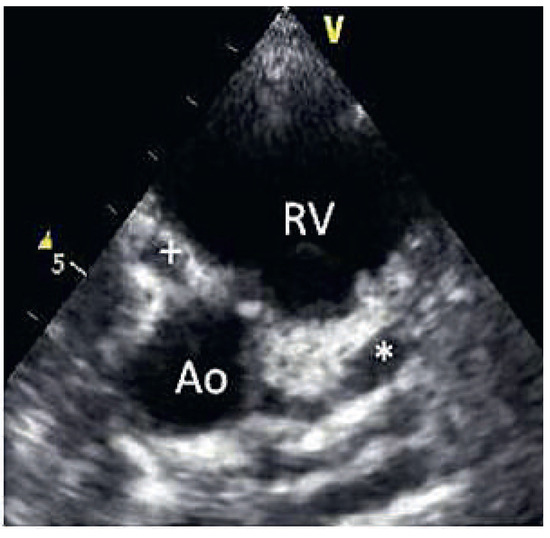

On the tenth day, we performed transthoracic echocardiography (Figure 1 and Figure 2), which revealed normal biventricular size and function, without hypokinesia. There was no pericardial effusion, no valvular disease, but a proximal enlargement of the left anterior descending coronary artery (LAD) was visualised. On the same day, because all these elements suggested Kawasaki disease (KD), treatment with intravenous polyvalent immunoglobulin (IVIG 2 g/kg as a single infusion: Privigen 70 g) and high-dose aspirin (80 to 100 mg/kg/d: 750 mg four times a day for eight days) was started, with rapid resolution of symptoms and apyrexia within 24 hours. Cardiac computed tomography (CT; Figure 3) showed three-vessel aneurysmal coronary artery disease (CAD) including a giant aneurysm of the proximal LAD (9 mm), an aneurysm of the circumflex artery (6 mm) and two aneurysms of the right coronary artery (4 and 5 mm). There was no vascular involvement in the cerebral and abdominal magnetic resonance imaging (MRI).

Figure 2.

2D echocardiography (* = LAD aneurysm, + = right coronary artery aneurysm).